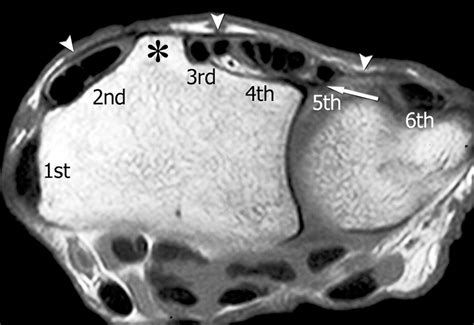

The following table outlines the contents of each of the six compartments, categorized by their specific tendon structures:

Compartment Primary Tendons Included

1st Compartment Abductor pollicis longus and Extensor pollicis brevis

2nd Compartment Extensor carpi radialis longus and brevis

3rd Compartment Extensor pollicis longus

4th Compartment Extensor digitorum and Extensor indicis

5th Compartment Extensor digiti minimi

6th Compartment Extensor carpi ulnaris